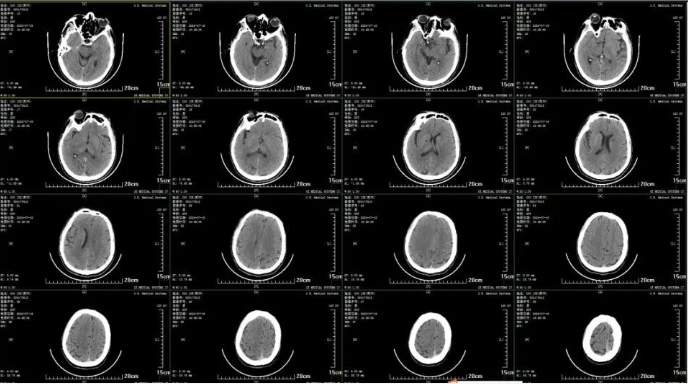

取栓后,患者脑部CT

术后复查CTA

术后一个月随访,患者日常活动正常

取栓后第二天,患者已神志清楚,眼球活动自如,各项生理反射活动正常。现已康复出院。出院一个月后进行随访,患者自述目前仅存在轻微头晕症状,生活自理且日常活动不受限。